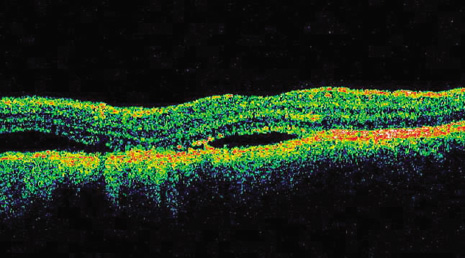

Approximately 6% of the Caucasian population manifests choroidal nevus.13 Choroidal nevi are managed by periodic observation. It is estimated that 1 in 5,000 choroidal nevi evolve into choroidal melanoma.14 Risk factors predictive of growth of small melanocytic lesions and their combined predictive values are listed in Tables 1 and 2 (Fig. 1). Documented growth of a melanocytic choroidal tumor is suggestive that the lesion is a choroidal melanoma. Because documented growth may be associated with worse systemic prognosis, some patients with small tumors that show three or more risk factors are treated promptly, without waiting for documentation of growth.12,15,16 On the basis of the few patients with medium-size choroidal melanoma who refuse treatment and are followed, natural history studies have found that there is greater mortality and higher risk of death.17

Fig. 1. Clinical risk factors for growth of small choroidal melanoma. (TFSOM = To Find Small Ocular Melanoma represents factors of Thickness over 2 mm, subretinal Fluid, Symptoms, Orange pigment, and Margin of tumor at optic disc) A. Thickness greater than 2 mm. Perimacular small choroidal melanoma measuring 2.9 mm in thickness and with overlying orange pigment and subretinal fluid, manifesting as retinal striae. B. Thickness greater than 2 mm. Optical coherence tomography demonstrating subfoveal fluid in the patient in A. C. Subretinal fluid. Sixteen-year-old patient with documented enlarging small choroidal melanoma and shallow subretinal fluid. D. Subretinal fluid. Optical coherence tomography demonstrating subfoveal fluid in the patient in C. E. Symptoms. Small choroidal melanoma producing symptoms of blurred vision from subfoveal fluid. Note the overlying orange pigment. F. Symptoms. Small choroidal melanoma located superiorly with trough of subretinal fluid in the foveola producing symptoms of metamorphopsia. G. Orange pigment. Macular choroidal melanoma with prominent overlying orange pigment and a rim of subretinal fluid. H. Margin at the optic disc. Minimally elevated small choroidal melanoma touching the optic disc. I. Other features. Juxtapapillary small choroidal melanoma with overlying orange pigment, shallow subretinal fluid, and irregular margins suggestive of tumor activity.